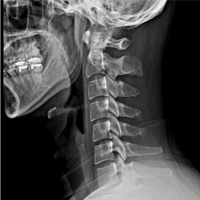

Diagnosis of Cervical Disc Herniation

If the symptoms persist for more than two weeks, it is recommended to visit a hospital for a proper diagnosis. At the hospital, a detailed medical history and physical examination will be conducted to differentiate from other conditions. Diagnostic confirmation can be made through imaging tests such as X-rays, CT scans, or MRIs.

• Normal Cervical X-ray:

Gentle C-shaped

curve